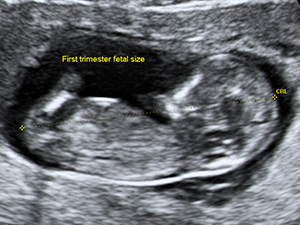

First Trimester